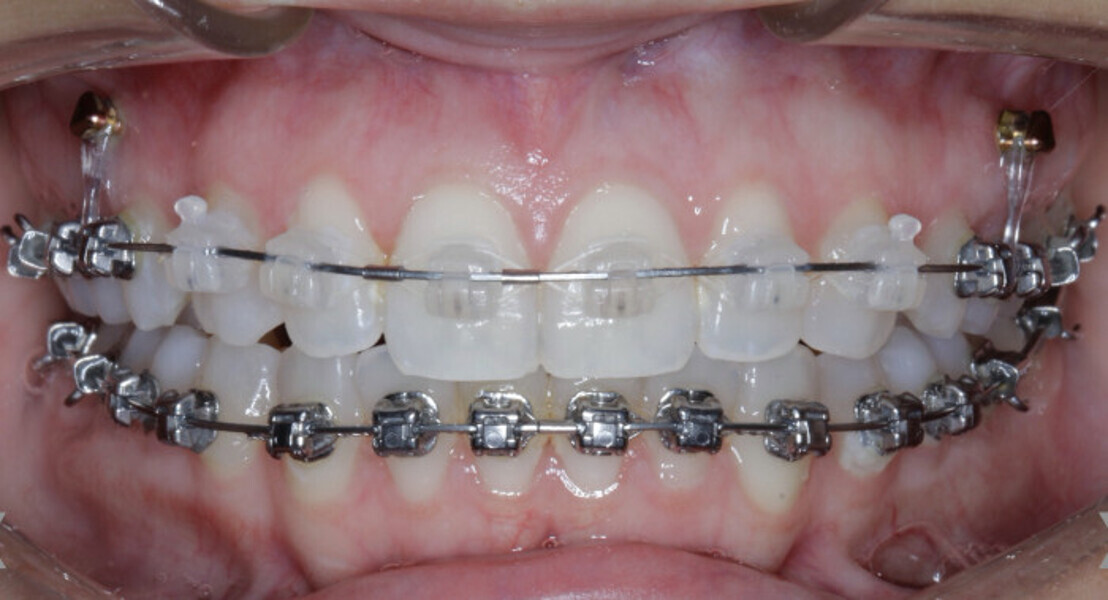

New Age orthodontics and orthopaedics with temporary anchorage devices